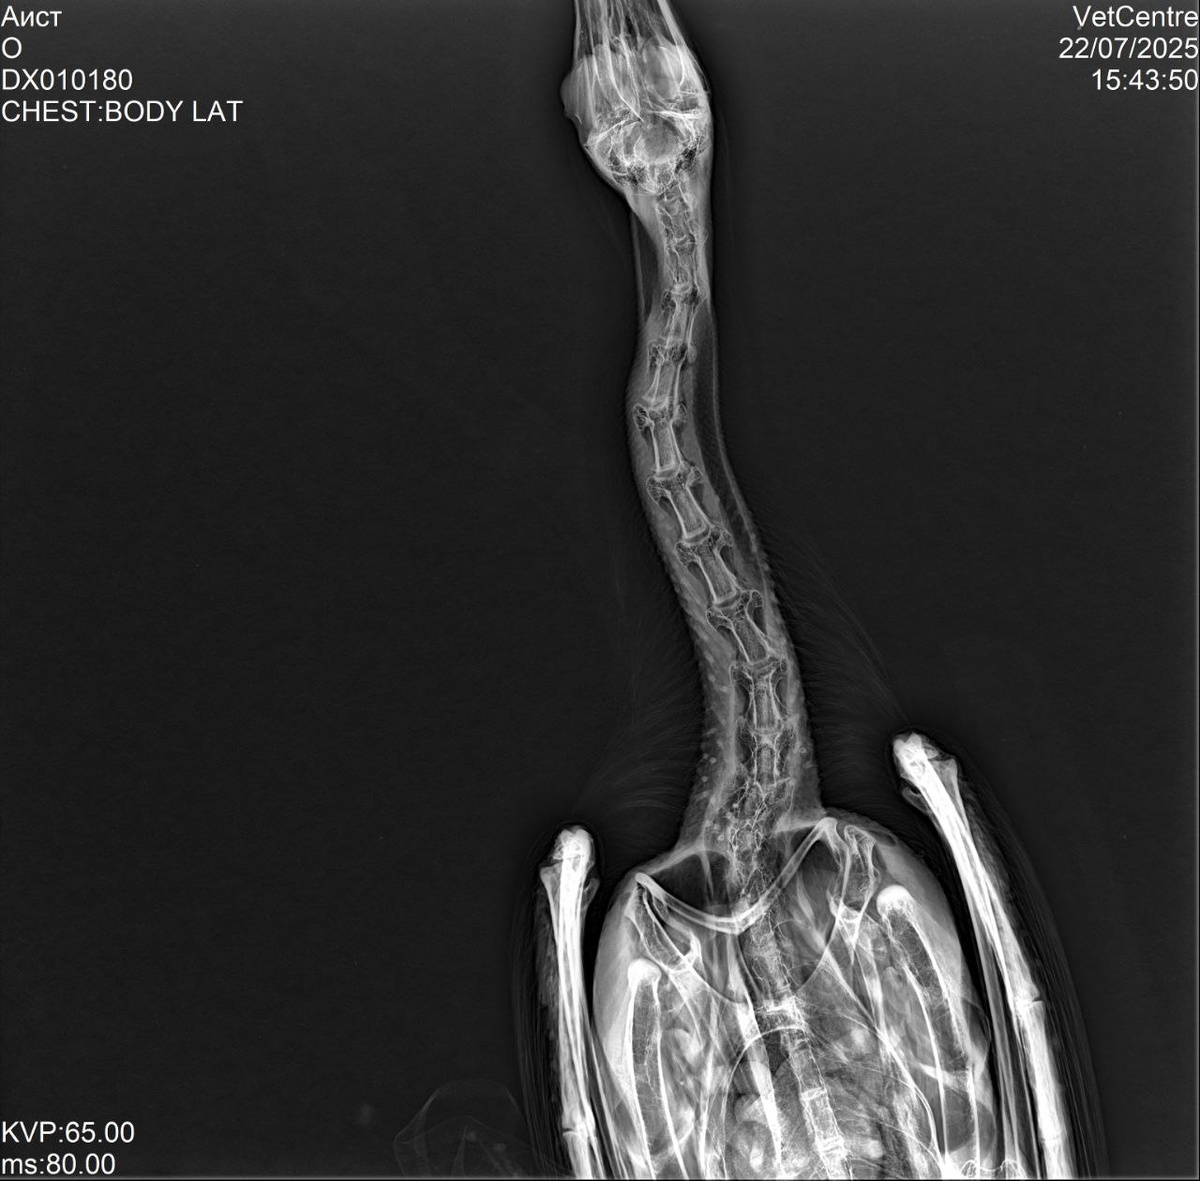

Рентген Аистенка Иваныча, травм нет, в остальном по состоянию завтра должно быть все понятно, если наши подозрения подтвердятся, то завтра он должен будет голову держать, держим за наши надежды кулачки! Дело в том, что сегодня после утреннего кормления, он срыгнул чернозеленую субстанцию вместе со съеденной рыбой, мы решили больше его не кормить и повезли к врачу, вчерашняя и сегодняшняя порция чиктоника смазала видно застрявшую гадость в пищеводе, эта гадость начала разлагаться и вызвала инфекцию. Если это так, то обильное кормление, ударная доза витаминных добавок и он еще в Африку слетает! Быть Добру!